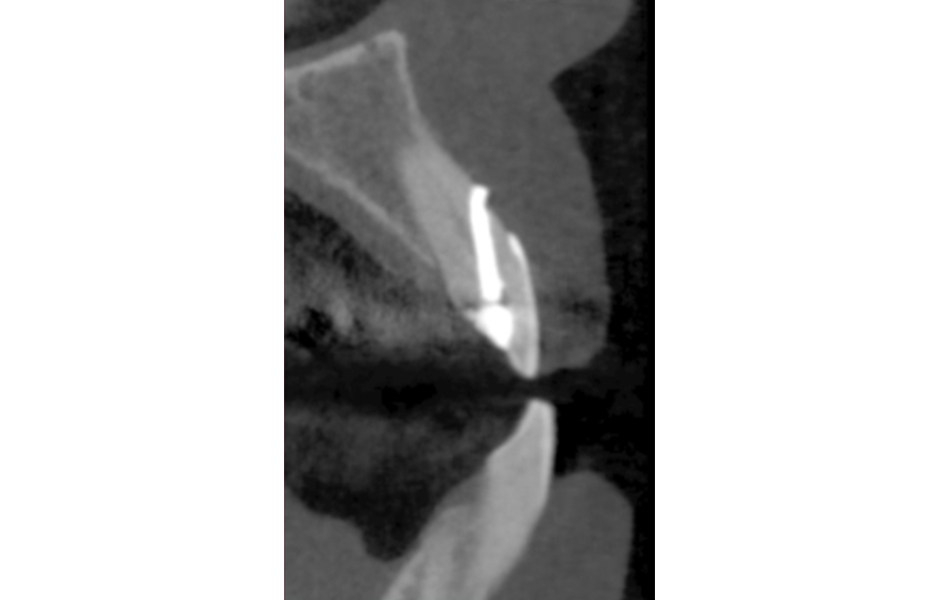

U delegovaného pacienta k reendodoncii udával ošetřující lékař neodstranitelnou kořenovou výplň. Před vlastním reendodontickým ošetřením jsem zhotovil CBCT (obr. 19, 20), abych vyloučil frakturu zubů a zhodnotil průběh kořenového kanálku. Pokud bychom zjistili vertikální frakturu nebo by průběh kořenového kanálku byl nepříznivý, nemělo by smysl se do výkonu pouštět.

U dalšího pacienta jsme zjistili zcestnou preparaci kořenového kanálku (obr. 21, 22).